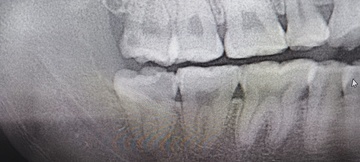

Before(下親知らずの抜歯前) 虫歯のある状態で埋まっている親知らず 抜歯前の骨の状態のレントゲン像

After(下親知らずの抜歯後) 横に生えた状態で埋まっている親知らずの抜歯後 虫歯がある親知らずの抜歯後 抜歯後の骨の状態のレントゲン像

原因をより詳しく調べるためパノラマレントゲンを撮影したところ、右下の親知らずは骨の中に埋まった状態のまま虫歯になり、隣接する歯を押しており、接触している奥歯の骨が溶けてしまっています。 そのため、右下の親知らずと隣の奥歯の間には、歯と歯ぐきの境目の溝である「歯周ポケット」が通常よりもかなり深くなっていました。

まず、親知らずと骨の中にある神経の位置、歯や周囲の骨の詳細な情報を確認するために、歯科用パノラマデジタル写真で口腔内を撮影します。撮影結果を踏まえ、抜歯方法や施術の難易度をしっかり確認しました。

1年後、取り除いた親知らず周囲の骨がしっかり再生したことを確認しました。